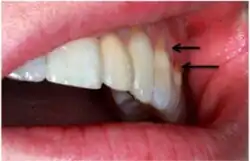

A systematic review by Teixeira et al. reported that most diagnoses of NCCL are derived from a combination of visual and tactile clinical examinations[11] under adequate illumination. This is depicted as a clinical loss of mineralized dental tissue at the cementoenamel junction (CEJ) in the buccal or lingual dental surfaces. There is also a consensus that visual dentine exposure is a reliable indicator of loss of tooth tissue.[14]